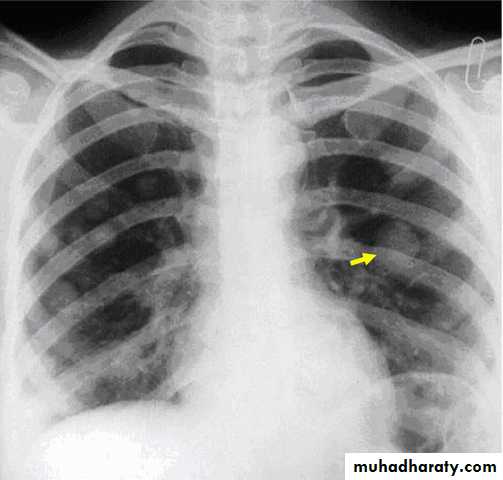

It is high but does not give useful distinction between mole and normal pregnancy. it is pivotal in diagnosis and follow up of GTD.Chest x- ray to exclude metastasis

Chest x ray

3. Chest x ray: If hCG titer plateau or rises.Chemotherapy is indicated if